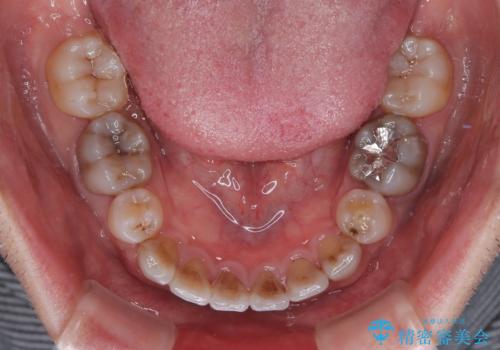

- 飛び出した前歯を気にして来院された患者様です。

口元を引っ込めるために上下左右の第一小臼歯4本を抜歯することとしました。

特徴的な歯の色が気になっているとのことで、今後セラミッククラウンによる審美歯科治療を検討されているとのことで、矯正治療の後戻りが落ち着いたタイミングで治療を進めていく予定です。